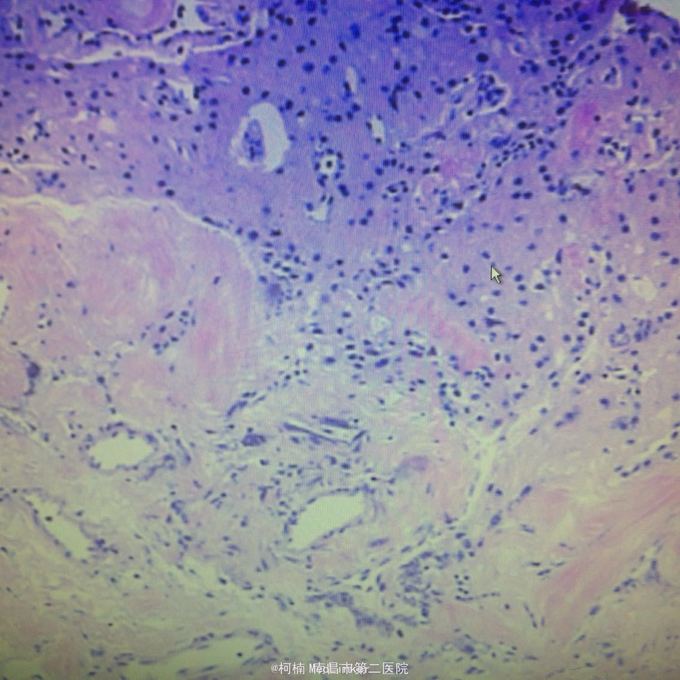

右侧额颞脑膜瘤 处理:全麻下行右侧额颞叶占位性病变切除术,术后病理提示:血管型脑膜瘤,WHO1级

随访:病人缓解出院。 讨论:血管型脑膜瘤是一种比较罕见的脑膜瘤类型,脑膜瘤在所有的颅脑部位肿瘤中占到五分之一左右,对于患者的健康会造成一定的影响。而血管型脑膜瘤血管废话藏丰富,对于其治疗会带来很大的困难,就如同血管瘤的手术治疗,术中非常可能会出血,且出血量较大,很难控制。